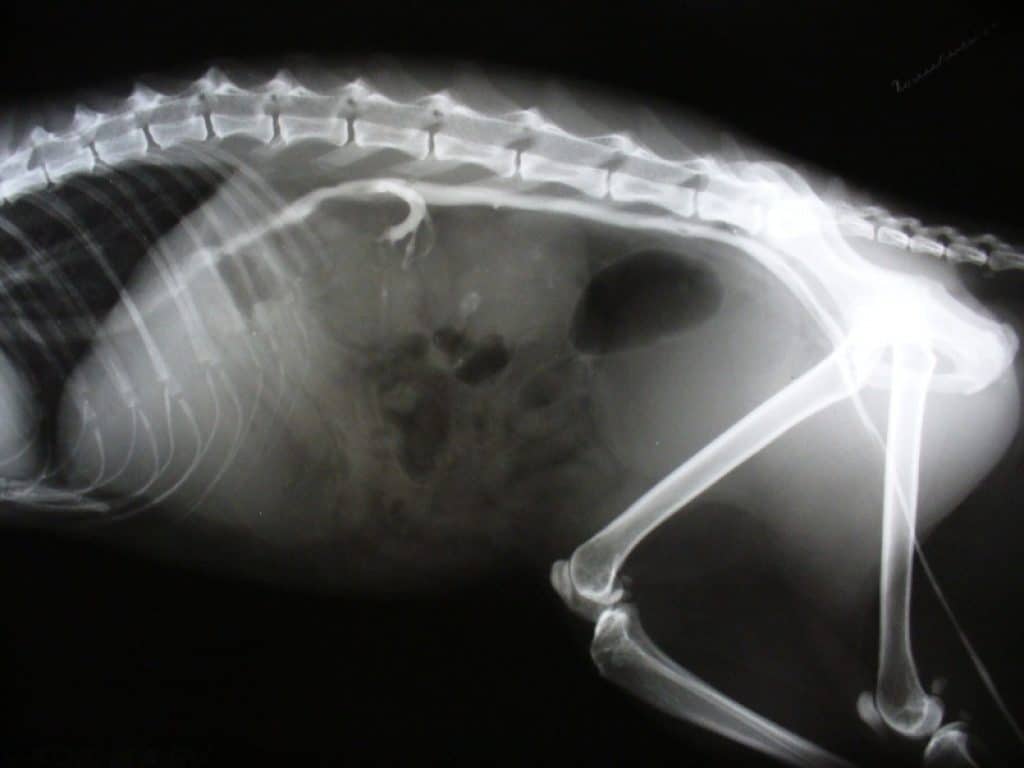

Рентгенологическое исследование

Определяется уменьшение размеров почек менее 2,5 кратной длины тела второго поясничного позвонка (L-2). Если наблюдается явный гиперпаратиреодизм, то видно снижение плотности костей, особенно верхней челюсти и кальцификация мягких тканей.